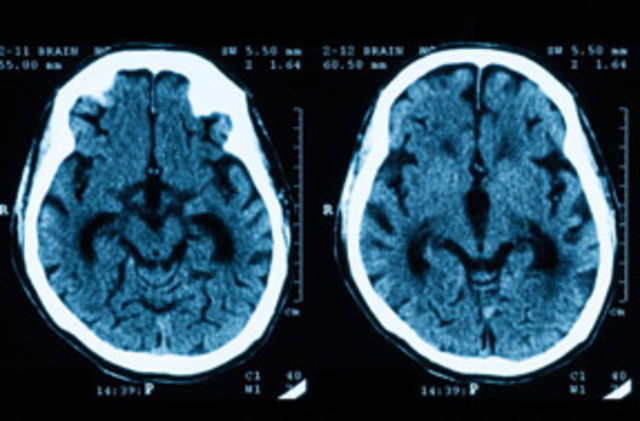

Se instala primer equipo de tomografía computarizada especializado en tomografías craneales a partir de ahí comienza la revolución radio diagnostica

• Escaneo craneal

Escaneo craneal

Se realiza el primer escaneo craneal en el hospital de londres